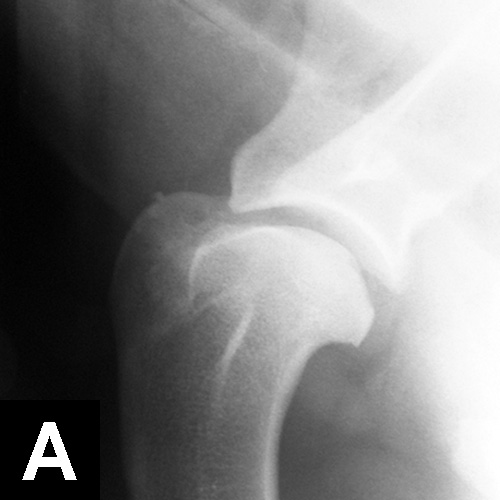

This pathology has a multifactorial etiology that affects the coxofemoral joint, most commonly in large-breed dogs (especially the German shepherd dog), but can also affect small-breed dogs and cats. Genetic and environmental factors can lead to joint laxity, which subsequently causes abnormal development of the acetabulum and femoral head, ultimately resulting in OA. Diagnosis in young patients is based on clinical signs (eg, difficulty in rising, swinging of the hindlimbs, pain, subluxation and laxity of the femoral head [Ortolani test]). Radiographic findings that confirm hip dysplasia are joint subluxation, incongruency, and early degenerative changes (Figure 1).

Figure 1. Ventrodorsal radiograph of the pelvis in a 12-month-old Labrador retriever with bunny-hopping and pain on extension of the hips. Bilateral coxofemoral subluxation and mild OA are evident.